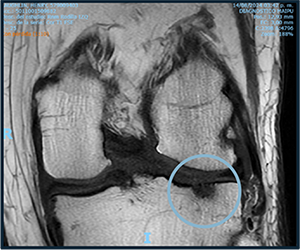

Before starting cell therapy, patients undergo a magnetic resonance imaging (MRI) or computed tomography (CT) scan to assess the condition of the bone and soft tissues of the knee.